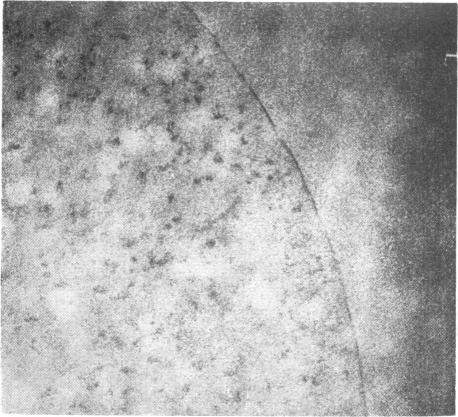

Association of cardiac pulmonary haemosiderosis and fibrosis.